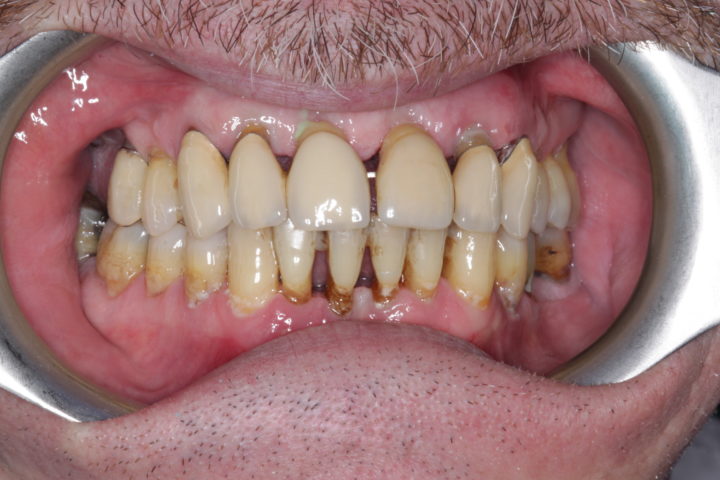

PRIMA

Caso risolto con Toronto Bridge - Fase iniziale, intermedia e finale